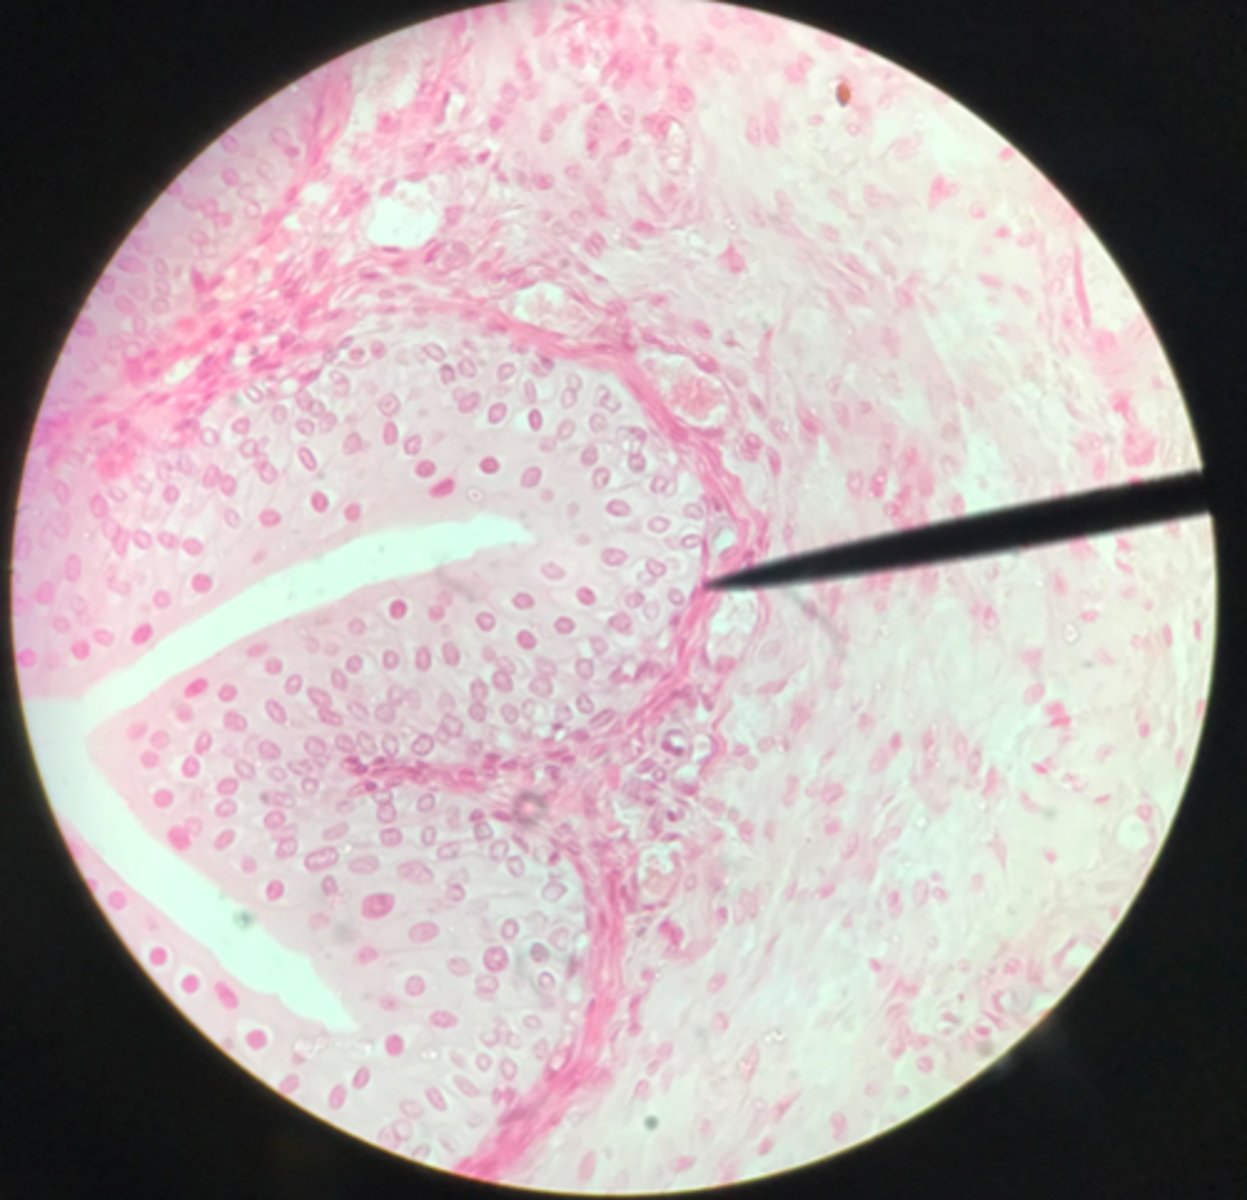

Transitional epithelium of the bladder

What tissue is depicted on the slide above the pointer?

Basement membrane

What cells of transitional epithelium are located where the pointer is at?

Ureter

Transitional epithelium

What structure/organ is depicted on this microscope slide?

What tissue makes up a majority of it?

Transitional epithelium

What type of tissue makes up the inner lining of the ureter?

Ureter

Note the smooth muscle layer surrounding the transitional epithelium

What organ is depicted on this slide?